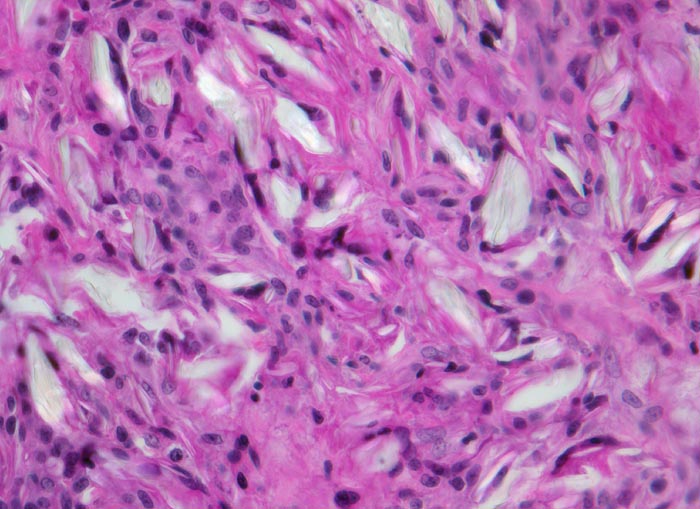

Fremdkörpergranulom

Artefakt / Fremdkörper / Pigment

Weichteile

Bindegewebe mit von histiozytärem Entzündungsinfiltrat und Einschlüssen von amorphem leuchtendem von Fremdmaterial, welches teilweise von Fremdkörperriesenzellen eingeschlossen ist.

Wegen fehlenden klinischen Angaben zu vorausgegangenen Operationen kann die Natur des Fremdmaterials nicht sicher angegeben werden.

Histologie

320